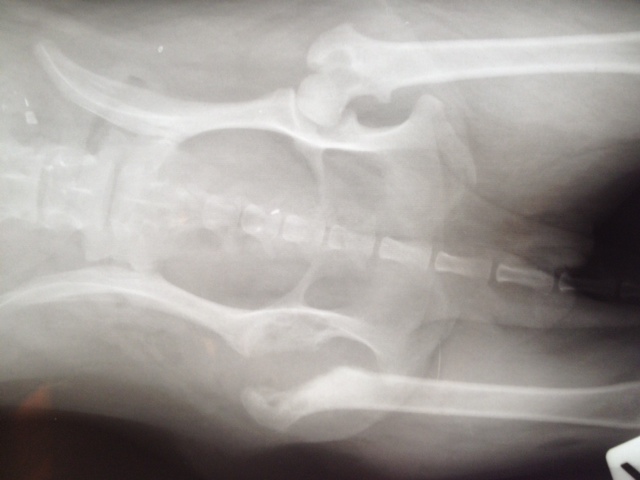

Aber Felipa ließ das eine Hinterbeinchen neuerdings so eigenartig hängen und trat nicht mehr damit auf. Also ließen wir es abklären. Es stellte sich heraus, dass sich der Knorpel des Oberschenkelhalskopfes zersetzt.

Die Ursache dafür sind genetisch bedingte Durchblutungsstörungen. Das kommt bei einigen kleineren Rassen vor. Es hat nichts mit der OP am Vorderbein zu tun.

Aber da Felipa das Hinterbein nicht ordnungsgemäß benutzen kann, musste sie also nun erst dort operiert werden, damit sie hinten auftreten kann, wenn das andere Vorderbein operiert wird.

Also hatte Felipa heute (01.08.) ihre 2.OP - allerdings wie gesagt ganz anders als geplant. Der Chirurg entfernte den kaputten Knorpel, wie man auch als Laie an den Aufnahmen gut erkennen kann.